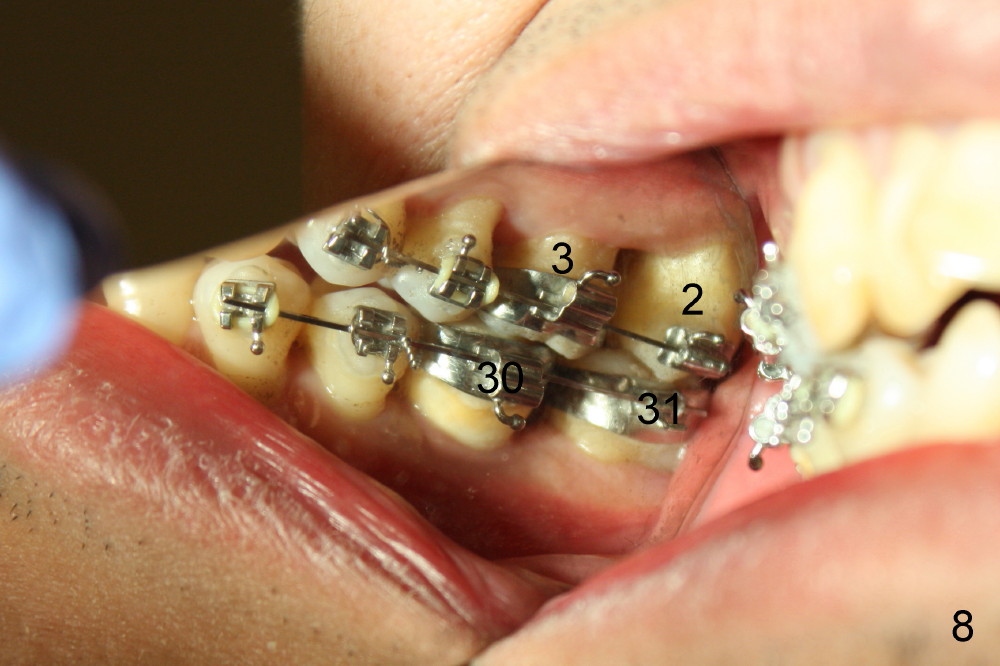

In 7 months, the right molar occlusion changes to Class I with normal overjet (Fig.8 mirror view). Class I posterior occlusion correction is evidenced by a gap between the teeth #30 and 31 (Fig.9 arrowheads) due to elastic retraction. There is no tension (bending) of wire between the teeth #2 and 3 in the final stage (Fig.10 arrowhead, as compared to Fig.7). A porcelain crown is subsequently cemented to the implant/abutment complex with occlusal equilibrium (Fig.11(mirror image) C). The remaining brackets and band are removed. Power chains in Fig.11 (arrowhead) were used to correct the rotation of the tooth #2 (Fig.10, bracket in the tooth was not well placed).